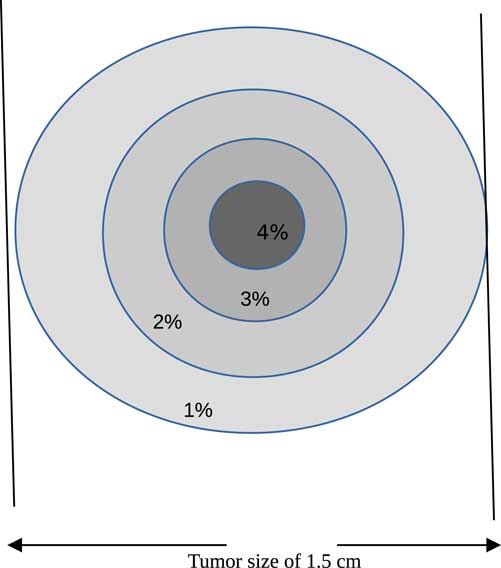

Proton therapy was simulated with the Monte Carlo code of a tumour within a human head. The tumour is assumed to have a spherical shape with a diameter of 1·5 cm and localised at the centre of the head (see Figure 1). The best way to inject NMs in a tumour localised in a sensitive organ like a human head is by the bloodstream. Carmeliet et al.Reference Carmeliet and Jain 21 and Avnesh et al. (2013)Reference Thakor and Gambhir 22 studied the development of blood vessels in the tumour cells; they noticed that the blood vessels are more concentrated in the centre of a tumour. Consequently, NMs will be distributed with a non-homogeneous way and concentrated more towards the centre of the tumour. In this simulation, the concentration of NMs in the tumour is assumed ranging between 0 and 4%. Figure 2 shows the concentrations of bio-NMs localised in a tumour taken in our simulation.

Figure 2 Distribution of bio-nanomaterials in tumour taken in our simulation.